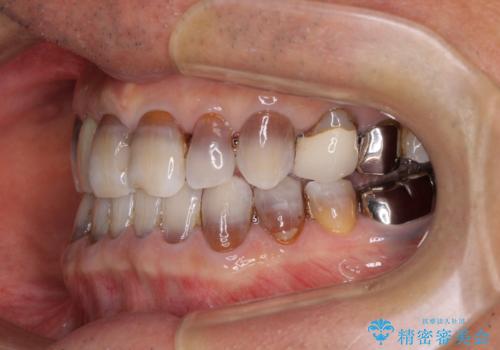

インビザラインは四六時中上下のマウスピースを介した咬合状態となるため、治療過程にて奥歯が接触しないという状態が続くことがあります。

奥歯の非接触は機能面において大きな障害であるため、この問題を解決しない限り矯正治療を終えることはできません。

インビザラインでの矯正治療が長期化してしまう要因の1つです。